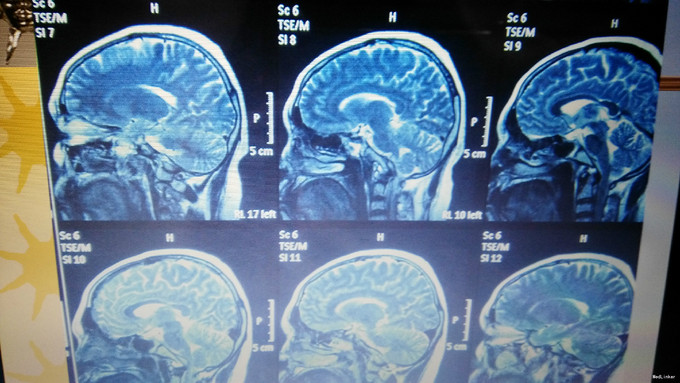

主诉:口渴多饮多尿35年,无月经来潮 现病史:患者6岁时无明显诱因出现口渴,大量饮水,多尿,曾在我院儿科就诊,诊断为“尿崩症”,给予垂体后叶素治疗,症状可好转,但患者未继续复查治疗,饮水量多于正常人每日饮水量。患者青春期时第二性征发育不明显,无月经来潮。20岁时于当地医院就诊,给予“黄体酮”治疗,可出现月经,量少,持续2-3天。患者未坚持服用药物,之后无月经出现。2年前开始多次出现鼻粘膜出血,量不详。患者有头痛、乏力症状,无头晕、视力模糊、无泌乳。

诊断:中心性肥胖(中度) 下丘脑综合征伴空泡蝶鞍综合征 治疗:患者垂体前叶功能减退,性腺轴计划给予人工月经治疗。

下丘脑综合征(hypothalamus syndrome)是由多种致病因素累及下丘脑,使其结构、代谢及功能受损。主要临床表现是下丘脑功能异常及轻微的神经、精神症状。多数病情较轻,发展缓慢,但常伴有精神和心理障碍,少数(如血管性和肿瘤性下丘脑综合征)病情进展较快,严重影响生活质量。